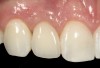

The crown and screw-retained custom abutment were removed, and a surgical cover screw was placed into the implant, thereby allowing spontaneous gingival augmentation in situ (Figure 33 and Figure 34). Note that the lingual aspect of the implant site was significantly more coronal than the labial aspect, which was positive because the defect would be limited to a facial–lingual defect. A fixed RBR bridge was cemented on the adjacent teeth and used as a tooth-supported transitional provisional restoration (Figure 35). A few weeks were allotted to let the soft tissue heal and migrate around the cover screw (Figure 36) to see if there would be complete coverage, thereby allowing a soft-tissue augmentation procedure to be performed with primary flap closure as in clinical scenario No. 2. The major obstacle in achieving a positive tissue response was that the implant depth was also deficient because the implant–abutment connection was at the level of the free gingival margin. It was decided that the best treatment option would be to remove the implant. A high-powered reverse-torque device (Fixture Remover Kit, NeoBiotech, www.neobiotechus.com) was used to remove the implant atraumatically (Figure 38 through Figure 41). The implant socket was allowed to heal for several months not unlike an extracted tooth (Figure 42). A new implant was placed in a better position from both a restorative and esthetic perspective (Figure 43), and after a few months of healing, a new crown was made (Figure 44). A satisfactory functional and esthetic result was achieved (Figure 45 and Figure 46) without employing pink porcelain.

Fig 45. The definitive crown tooth No. 26 seated in place and provisionally cemented. The recession defect was eliminated with the removal and replacement of a new implant in the proper position.

Figure 45

Fig 46. The post-treatment radiograph showing a healthy stable implant and restoration.

Figure 46